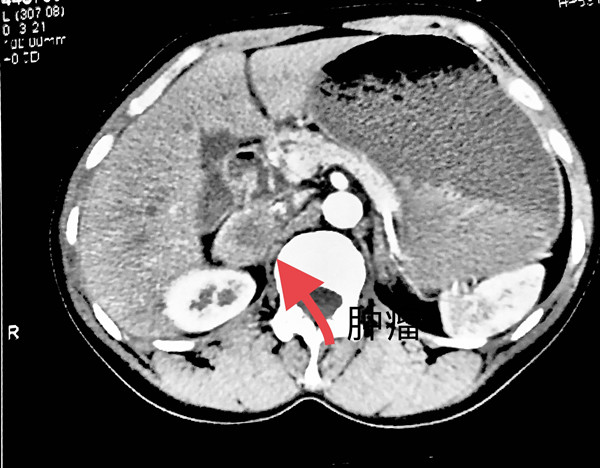

1月多前,阿旦因身体不适前往九师医院检查发现患有肾上腺肿瘤,需要手术治疗。此病术前准备复杂,术中血压波动剧烈,肿瘤位置深在,手术风险较高,泌尿外科刘卫洪主任考虑以往从未开展过此类手术,为求稳妥,建议上转省城大医院救治。但对阿旦来讲,家在额敏县,乌鲁木齐远在千里之外,异地就医的路费、陪护住宿以及住院费用等下来可不是一笔小数目,真是难坏了一家人。

8月27日上午,由兵团九师医院泌尿外科刘卫洪主任主刀,“助手”薛玉泉从手术入路选择、解剖层面辨别、手术操作步骤、术中注意事项等方面给予全程指导,兵团九师医院首次独立完成后腹腔镜下肾上腺肿瘤切除术。手术过程顺利,用时1小时,出血20ml,术中患者血压平稳,术后患者恢复良好。整个诊疗精准的犹如时钟,一台极具挑战性的手术就这样“风平浪静”的结束了。